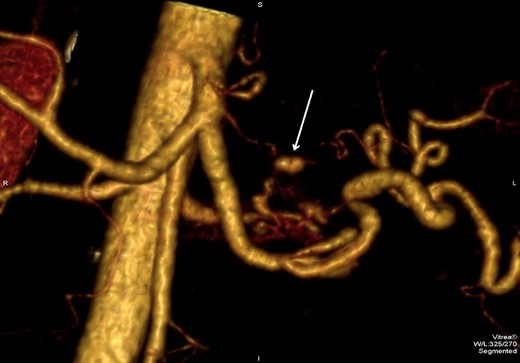

However, 4 days after the ultrasound guided injection, the patient collapsed on the ward with haematemesis and hypovolaemic shock. He was resuscitated initially with intravenous fluids and transfusion of blood products and remained alert with no abdominal signs. An emergency gastroscopy showed a 1.5 cm gastric ulcer on the posterior gastric wall with a large clot in the upper stomach but no active bleeding. A repeat CT abdomen demonstrated persistent flow in the pseudoaneurysm (Fig. 4).

CT abdomen image post thrombin injection shows flow in the pseudoaneurysm (arrow).

3D reconstruction images of the CTA revealed that the pseudoaneurysm was localized on an unnamed vessel branching directly from celiac trunk (Fig. 5). This deemed not suitable for endovascular embolization due to its size.

3D CTA reconstruction demonstrates the pseudoaneurysm (arrow) originating from the unnamed vessel.